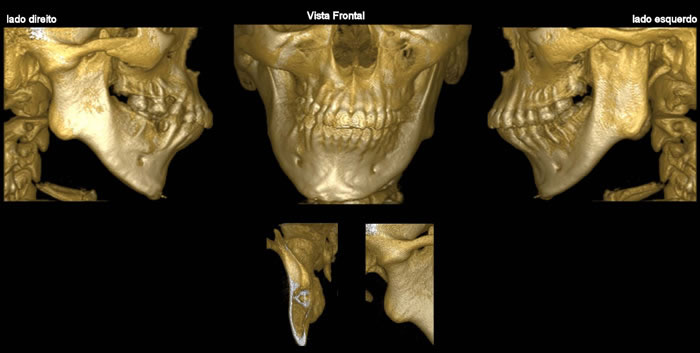

Caso 1: Anquilose de ATM

Paciente com assimetria, limitação de abertura bucal. Observa-se união óssea da porção posterior e lateral do côndilo ao esfeóide e zigomático.

Caso 3: Fratura de ATM

Paciente com história clínica de trauma. Fratura no côndilo direito com deslocamento do fragmento para medial e deslogamento do côndilo para lateral da cavidade articular.